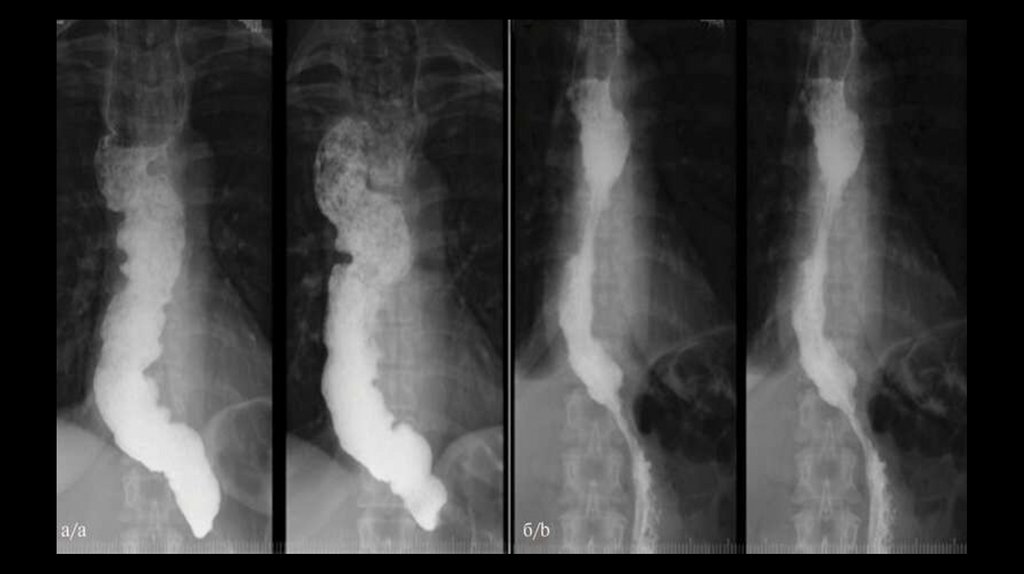

(Слева) Продольно ориентированные бляшки слизистой оболочки, характерные для

кандидозного эзофагита. (Справа) На рентгенограмме пищевода с двойным контрастированием

визуализируются дефекты наполнения, расположенные продольно, которые обусловлены

наличием бляшек. Рентгеноскопия с двойным контрастированием является очень точным

методом в выявлении характерных поражений пищевода при кандидозе: бляшек, язв, и менее

типичных проявлений кандидозного эзофагита.